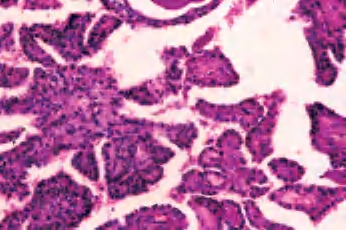

(3)嗜酸细胞亚型:大体特征是特有的红棕色外观,可呈乳头状或滤泡样结构,镜下乳头是由嗜酸细胞衬覆纤维血管间质形成,含有丰富的慢性炎细胞,常伴有桥本甲状腺炎。癌细胞呈多角形,也可以是柱状,细胞核的特征与通常的乳头状癌相似(图3-48至图3-50)。

图3-48 甲状腺乳头状癌,嗜酸细胞亚型

图3-49 甲状腺乳头状癌,嗜酸细胞亚型

图3-50 甲状腺乳头状癌,嗜酸细胞亚型